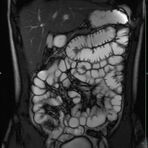

Sellink

• Dünndarm/Dickdarm

• Chronisch-entzündliche Darmerkrankungen wie Morbus Crohn oder Colitis ulcerosa. Beurteilung der Ausdehnung der Entzündung, Darstellung von Fisteln oder Abszessen bzw. einer Passagebehinderung (MR-Sellink, MR-Kolonographie, beide Untersuchungen nach spezieller Vorbereitung)

• Darstellung bzw. Kontrolle im Verlauf bei perianalen Fisteln und Abszessen

• Verlaufskontrolle des Lokalbefundes nach Rektumentfernung bei Karzinom